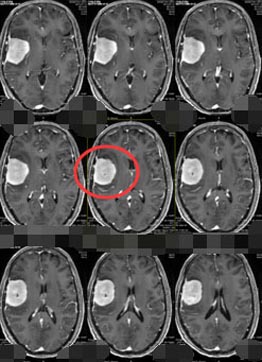

入科时查体:反应迟钝,言语缓慢,记忆力、理解力明显变差,右侧肢体肌力V级-,右侧肢体不自主抖动。头颅MR检查结果示:右侧额颞部颅骨内板下占位性病变,考虑脑膜瘤可能性大。头颅CTA检查结果示:右侧额颞部占位性病变血管较丰富,病变推压右侧大脑中动脉远端分支侧呈抱球状改变。

排除手术禁忌症、积极完善术前准备后,由鲁明副院长主刀行“右侧颞部巨大占位性病变切除术”,术中可见肿瘤呈灰褐色,质软,边界不清,血供丰富,肿瘤内侧包绕颈内动脉、后交通动脉,后方与脑干粘连紧密,分离困难,仔细分离鞍区及脑干周围肿瘤,显微镜下全切肿瘤,手术完成顺利。